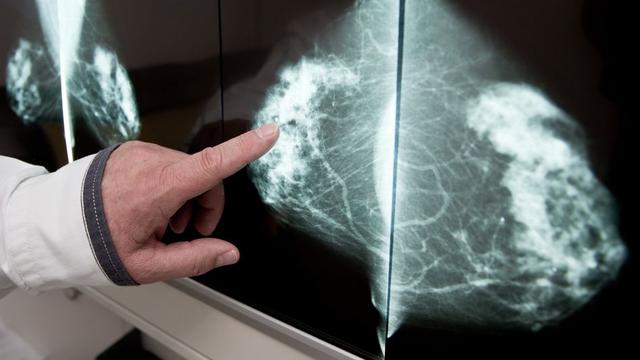

Die Mammographie ist eine Röntgenuntersuchung der Brust und gilt als beste Methode zur Abklärung von auffälligen Symptomen. Sie wird auch zur Früherkennung von Brustkrebs eingesetzt, um kleine, noch nicht tastbare Knötchen oder Mikrokalk zu erkennen. Heutzutage wird bei der Mammographie fast ausschließlich ein digitales Röntgenverfahren verwendet, bei dem die Bilder direkt im Computer gespeichert und betrachtet werden können.

Die Mammographie ist eine Röntgenuntersuchung der Brust, die sowohl zur Abklärung von auffälligen Symptomen als auch zur Früherkennung von Brustkrebs eingesetzt wird. Sie ermöglicht die Erkennung sehr kleiner Knoten oder Mikrokalk, die oft ein Vorstadium von Brustkrebs darstellen. Heutzutage wird fast ausschließlich ein digitales Röntgenverfahren verwendet, bei dem die Bilder direkt im Computer gespeichert und betrachtet werden können. Die Aufnahmen werden im Stehen gemacht, indem die Brust zwischen zwei Plexiglasplatten gepresst wird, um das Gewebe möglichst dünn zu machen und das Röntgenbild besser beurteilen zu können. Die Untersuchung kann unangenehm und etwas schmerzhaft sein. Sowohl bei Frauen mit Implantaten als auch bei Frauen nach den Wechseljahren ist die Mammographie problemlos und sicher möglich. Es wird empfohlen, vor der Untersuchung auf Deos zu verzichten, da sie einen Schleier auf der Haut hinterlassen können, der in der Röntgenaufnahme sichtbar ist. Der beste Zeitpunkt für Mammographien liegt in der ersten Zyklushälfte, während der Periode oder in der ersten Woche danach, da die Brust dann weniger empfindlich und weicher ist. Wenn es um die Auswertung der Röntgenaufnahmen geht, hängt die Sicherheit des Arztes unter anderem von der Dichte des Gewebes ab. Bei jüngeren Frauen oder solchen, die hormonhaltige Medikamente einnehmen oder stillen, kann die Röntgenaufnahme möglicherweise weniger aussagekräftig sein. In solchen Fällen kann es sinnvoll sein, die Medikamente im Monat der Untersuchung abzusetzen oder andere bildgebende Verfahren zu nutzen. Wenn der Befund der zweidimensionalen Mammographie unklar ist oder eine Stelle nicht gut diagnostizierbar ist, kann ein modernes dreidimensionales Mammographie-Verfahren namens digitale Brust-Tomosynthese (DBT) verwendet werden. Die DBT ist sensitiver als die herkömmliche 2D-Mammographie, hat aber auch mehr falsch positive Befunde zur Folge.

Die Mammographie ist eine Röntgenuntersuchung der Brust, die sowohl zur Abklärung von auffälligen Symptomen als auch zur Früherkennung genutzt wird. Sie ermöglicht die Erkennung sehr kleiner, noch nicht tastbarer Knötchen oder Mikrokalk, die ein Vorstadium von Brustkrebs sein können.